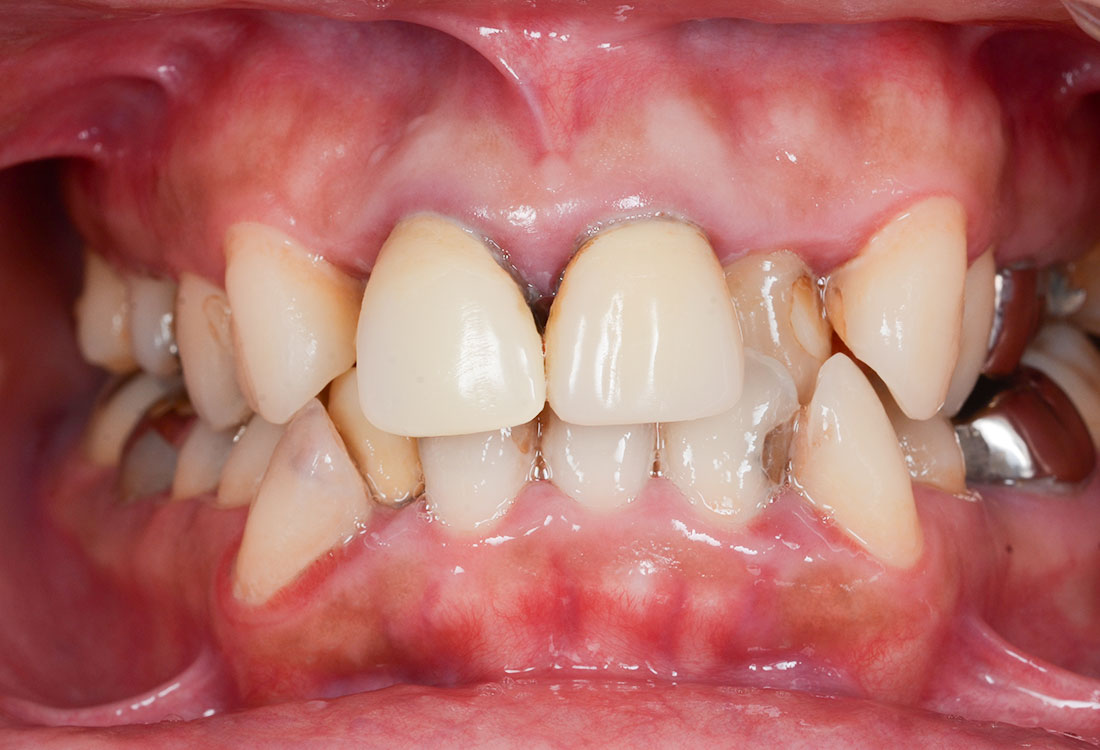

ご相談内容

- 上の左右2番目の歯と尖っている前歯が気になる

- 歯の形を治したい

- 歯の色をきれいにしたい

ホワイトニングで全体的に白くした後、その色に合わせて被せ物を作っていきます。

治療内容

模型を作成して最終的な形を模索します。

ファイバーコアで神経のない歯に土台を作ります。

ファイバーコアは保険治療で使われるメタルコアと異なり白く、被せ物が透けて黒く見えません。

土台になる歯の形を整えて最終的な形の模型を作ります。

治療後

白く明るい口元になりました。